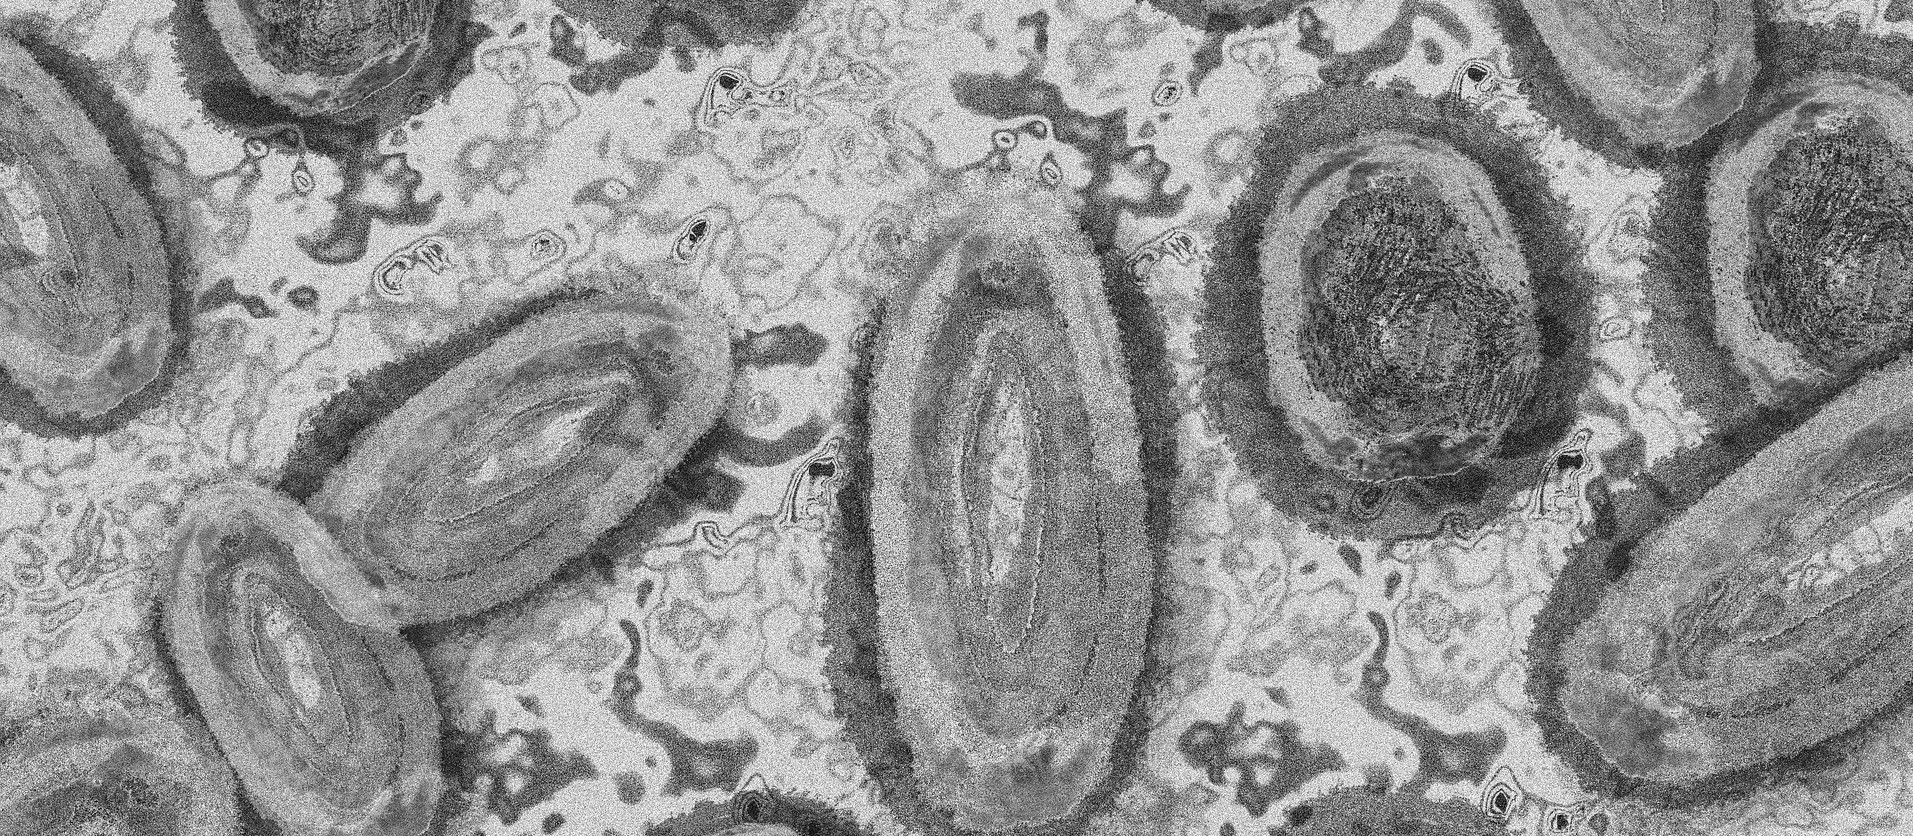

Imagem Ilustrativa/Representação abstrata do vírus da varíola/Gerd Altmann/Pixabay

De acordo com o novo boletim epidemiológico da Monkeypox, divulgado nessa terça-feira (30) pela Secretaria de Saúde de Londrina, a cidade confirmou mais três casos da doença na cidade. Ao todo já foram confirmados seis casos de varíola dos macacos em Londrina, quatro deles permanecem em isolamento.